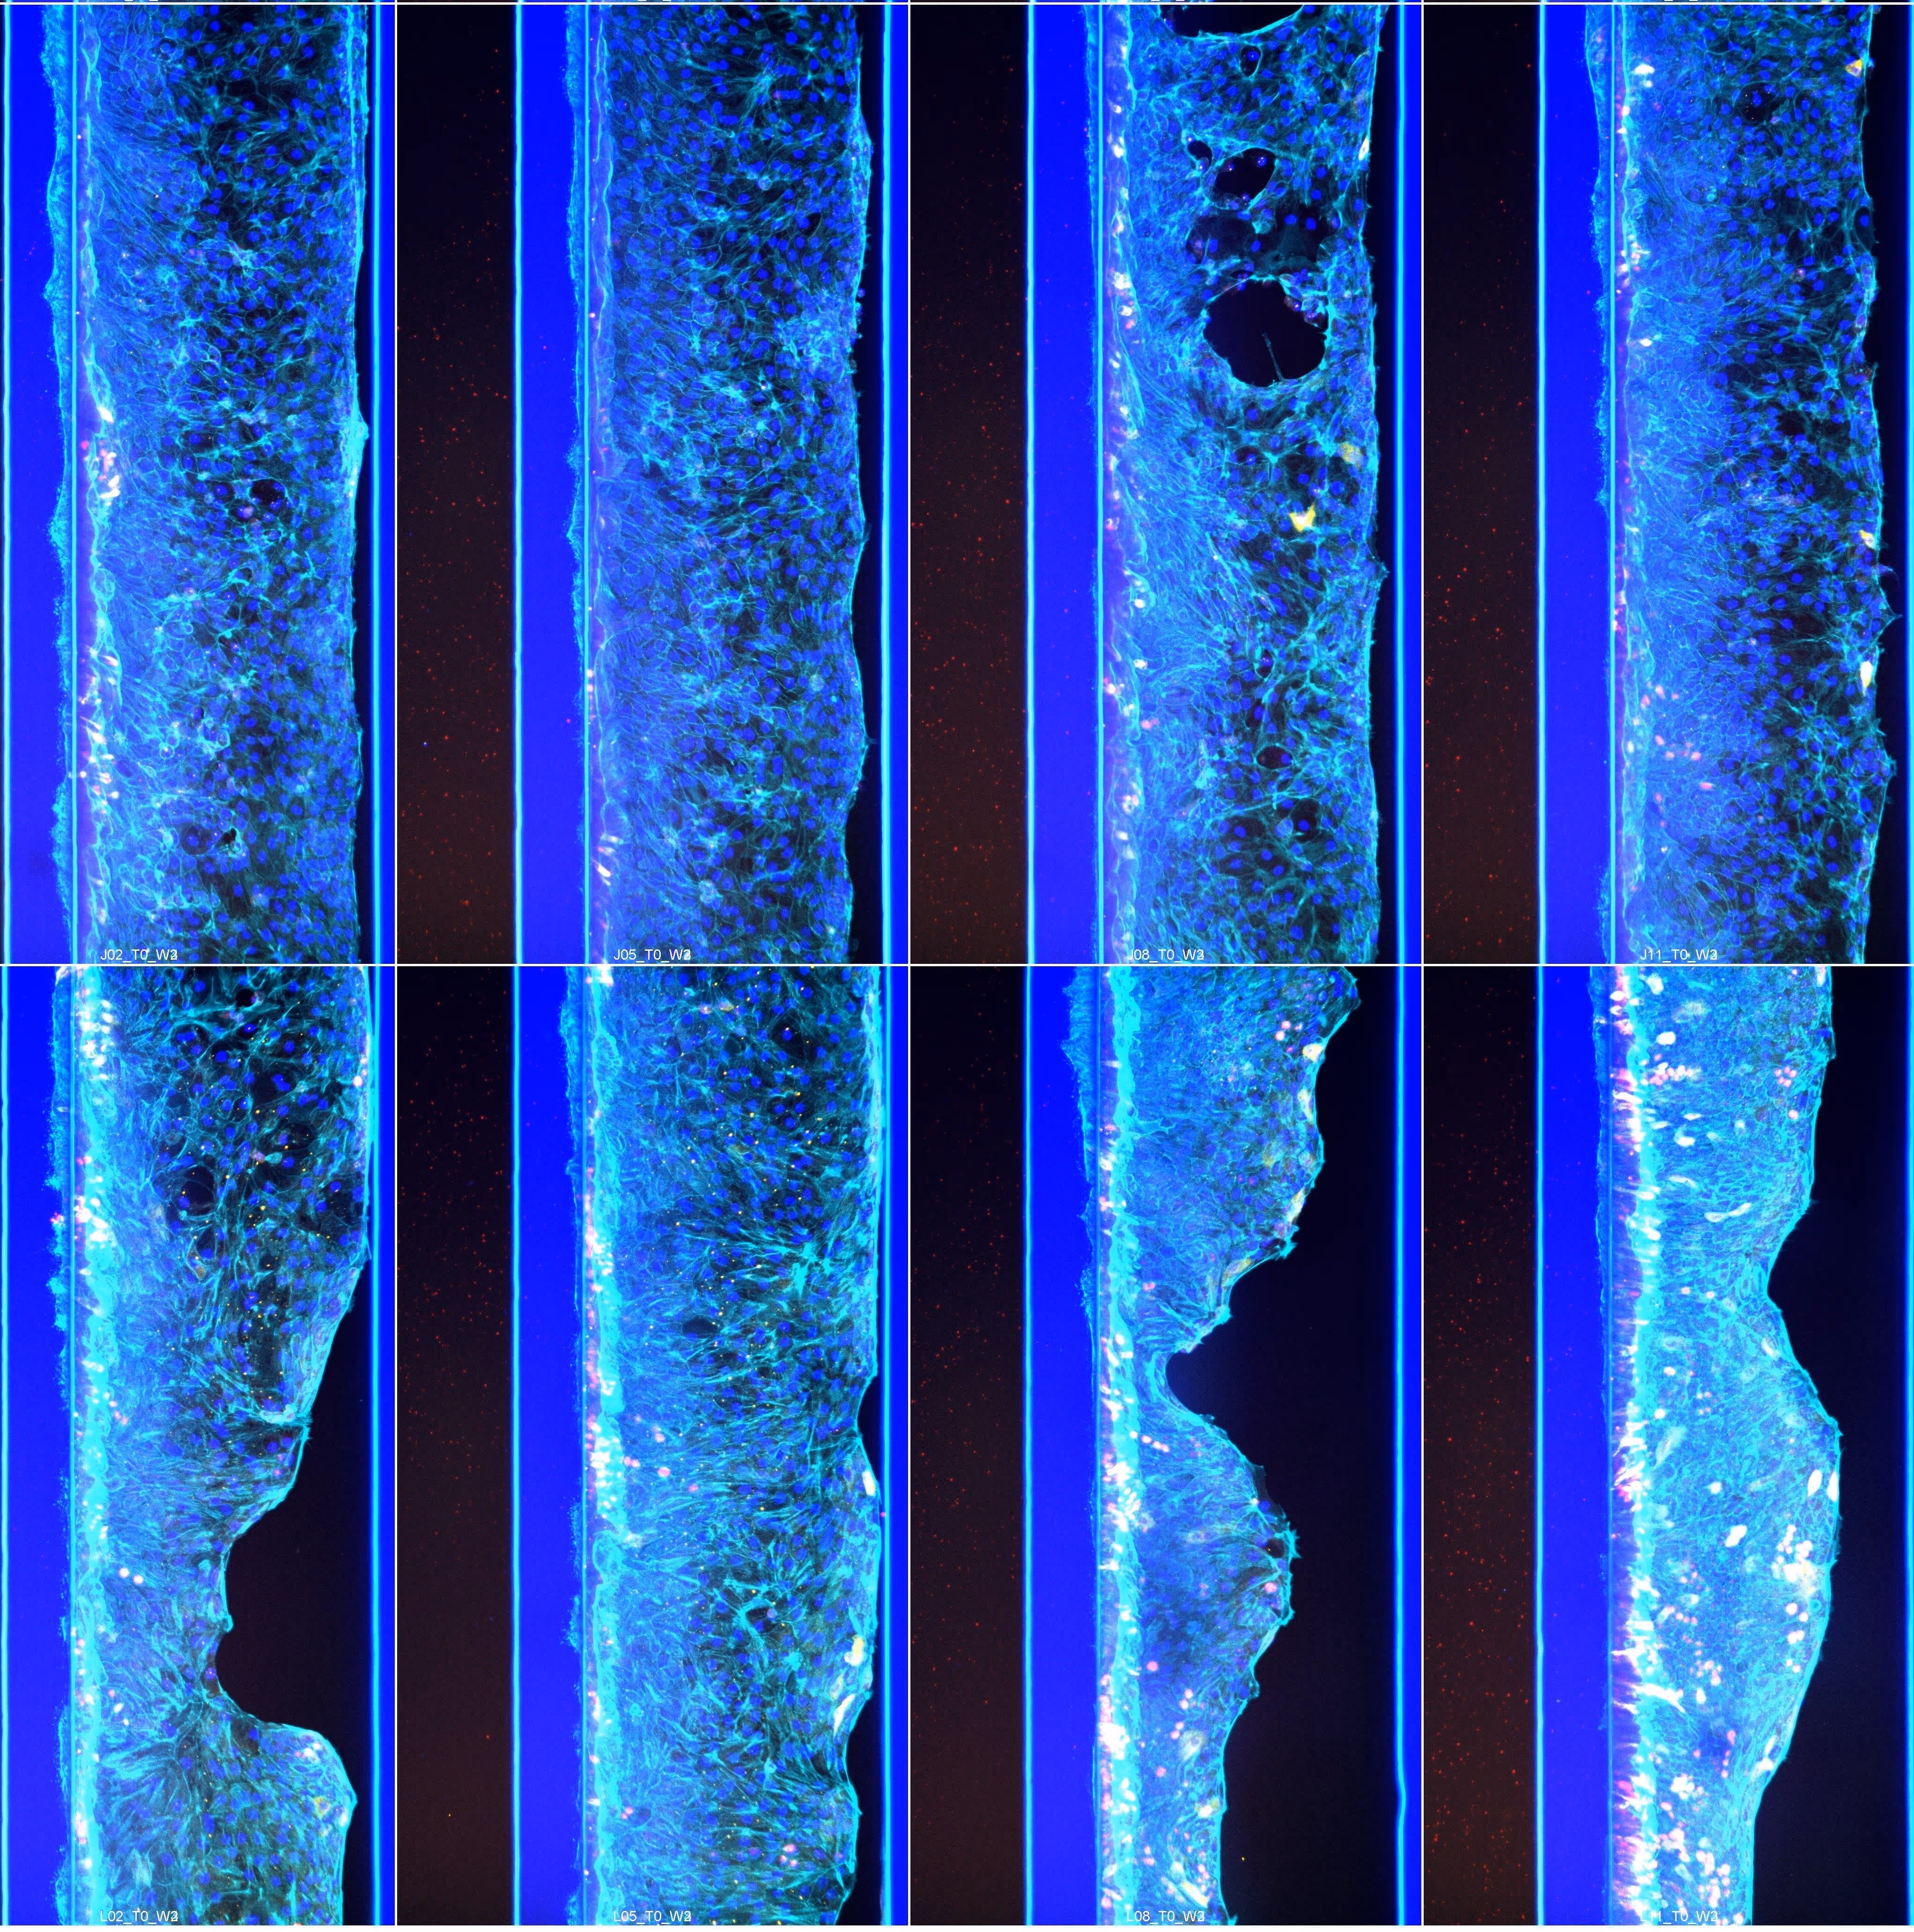

The OrganoReady® Colon Organoid is an adult stem cell–derived, ready-to-use HUB colon organoid model delivered as perfusable, leak-tight tubules with a functional intestinal barrier. This assay-ready format enables accurate and reproducible gastrointestinal (GI) toxicity testing, addressing a critical need in preclinical drug development.

The OrganoReady Colon Organoid model demonstrates adult intestinal tissue characteristics, including a mature epithelial phenotype with apical–basolateral polarity, functional transporter activity, and proliferative profile.

Organoid tubules comprise all major gut cell subtypes, including enterocytes, goblet cells, proliferative cells, and stem cells

Long-term viability and reproducible barrier function (TEER) that can be modulated with toxicants